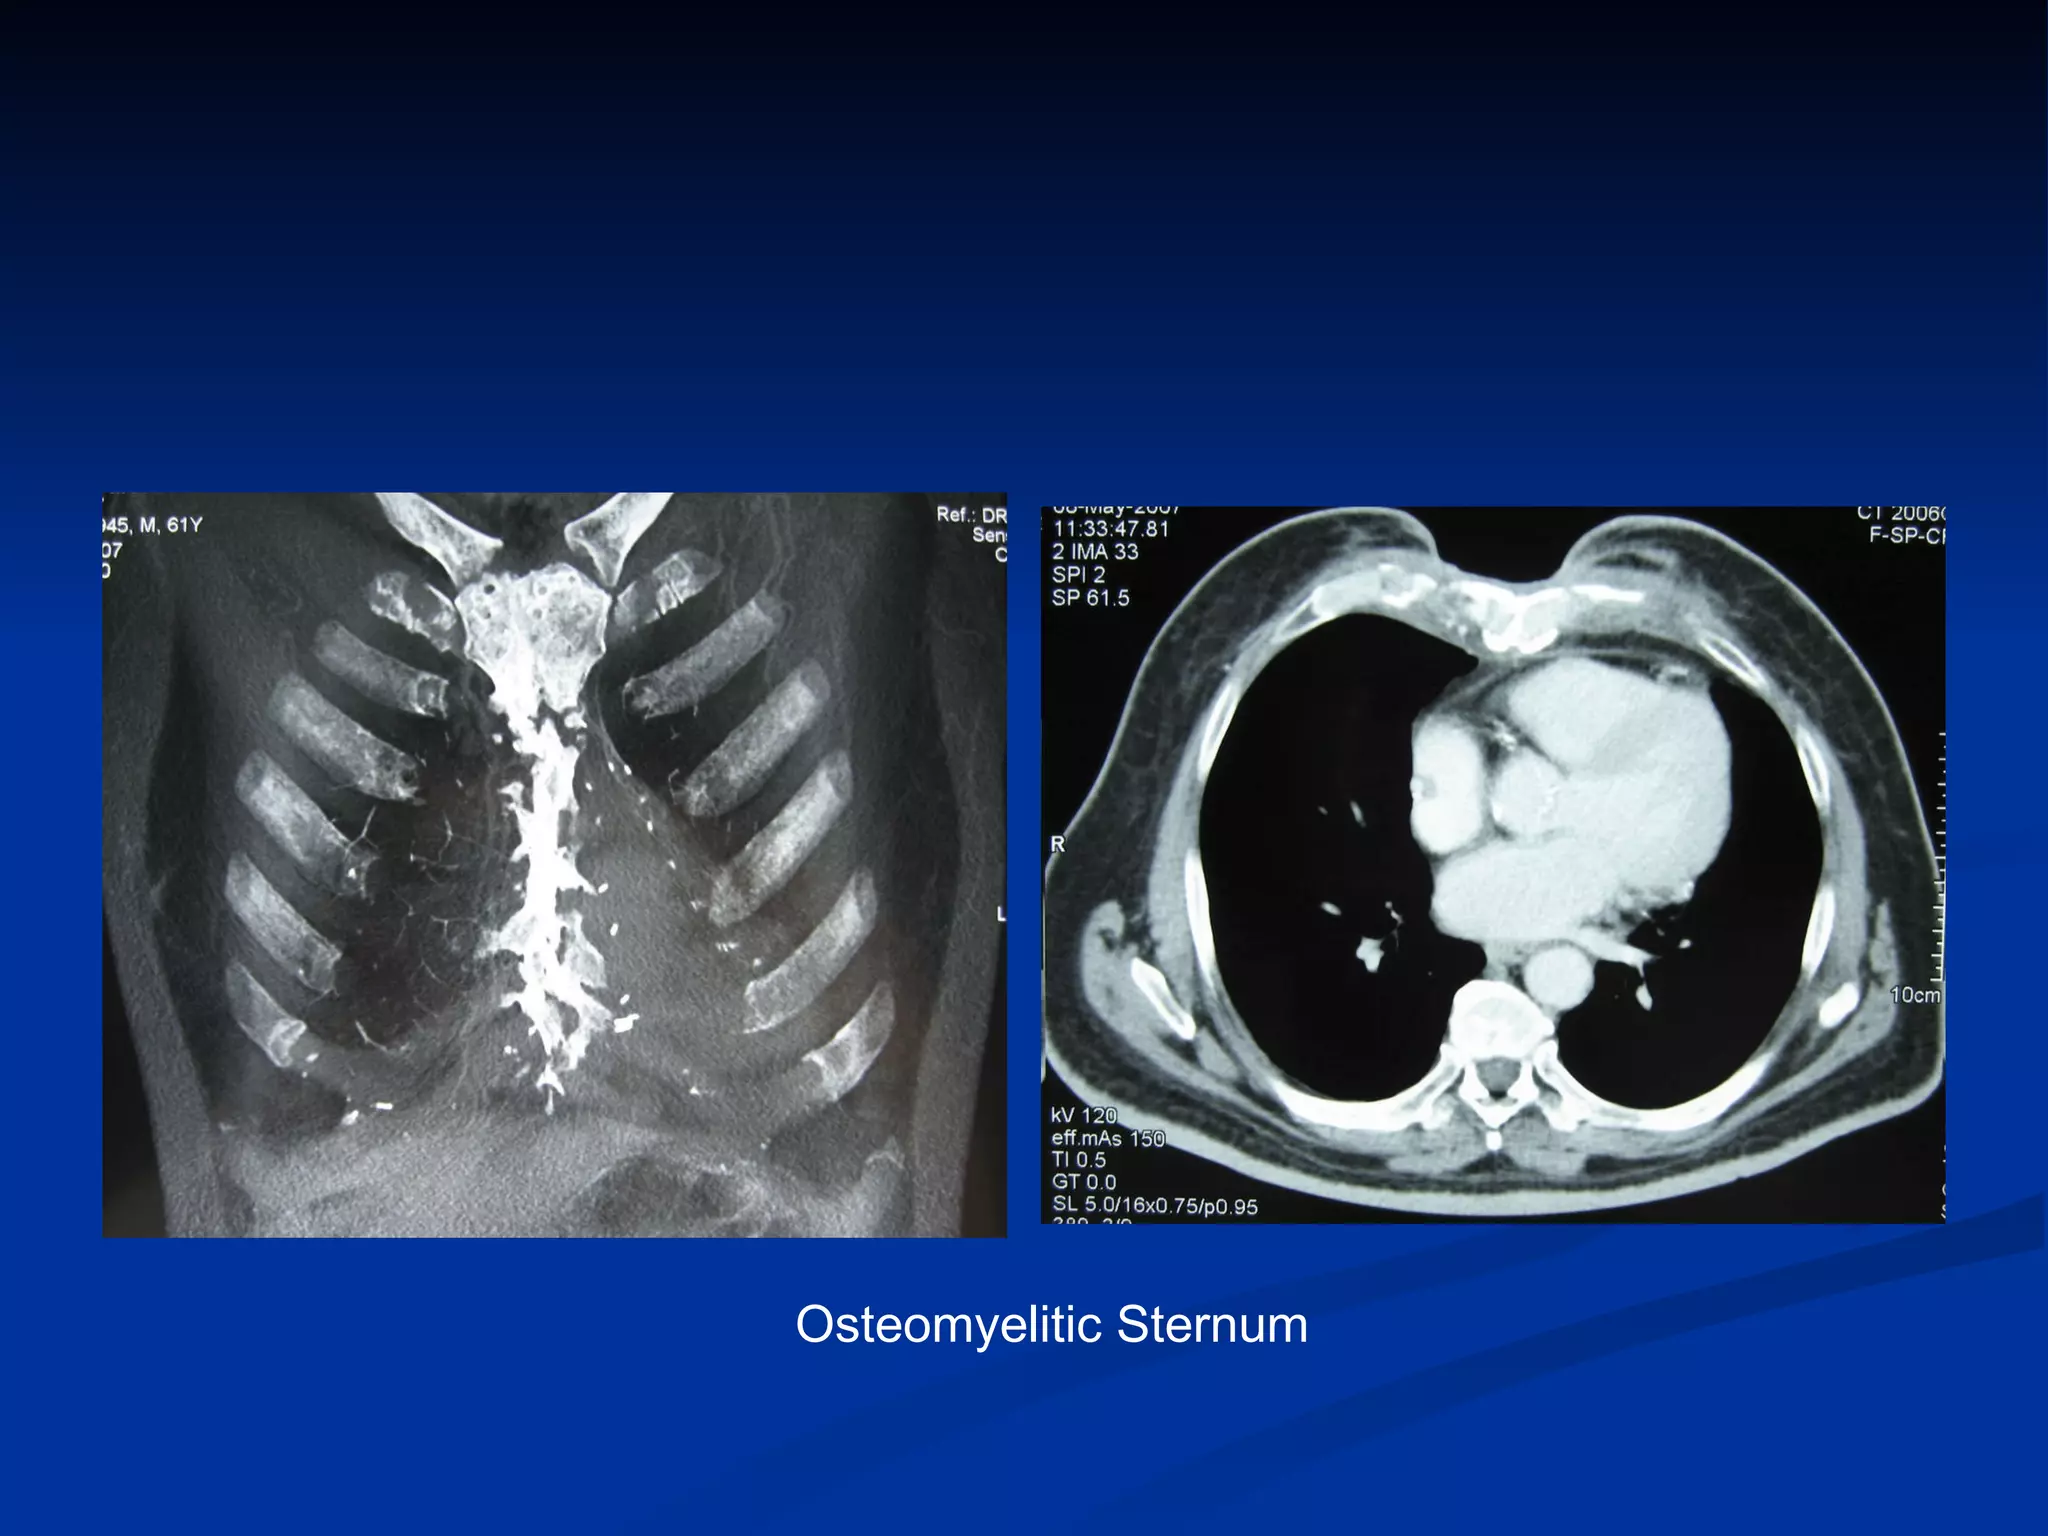

How to make an early diagnosis The  Classic symptoms  and signs of acute infection are  infrequently  encountered   Fever and Leukocytosis  in the absence of local symptoms or signs may be the only presenting clinical features in a small percentage of patients  Wound discharge  is the most common presentation and occurs in 70% to 90%  Local symptoms include wound pain, tenderness, and sternal instability  Chest roentgenograms  are rarely helpful in the early diagnosis  Chest computed tomography scanning with mediastinal aspiration

Osteomyelitic Sternum

How to makean early diagnosis The Classic symptoms and signs of acute infection are infrequently encountered Fever and Leukocytosis in the absence of local symptoms or signs may be the only presenting clinical features in a small percentage of patients Wound discharge is the most common presentation and occurs in 70% to 90% Local symptoms include wound pain, tenderness, and sternal instability Chest roentgenograms are rarely helpful in the early diagnosis Chest computed tomography scanning with mediastinal aspiration